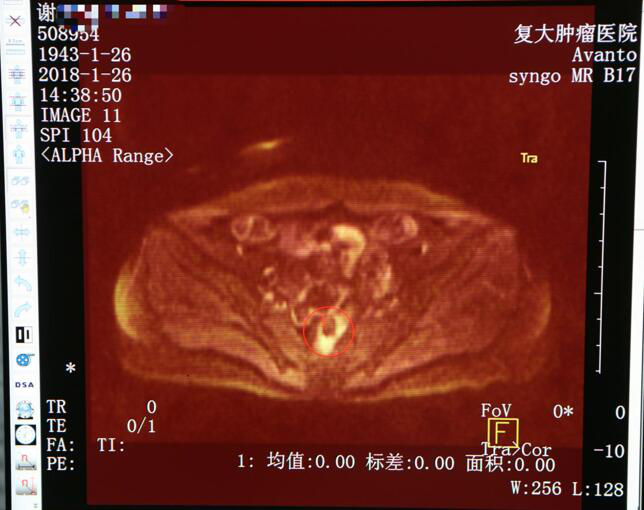

Снимок МРТ после лечения

28 августа 2017 года дама Се приехала в больницу Фуда. После консультации с экспертом по опухолям ей сообщили, что нет необходимости делать временную стому, поэтому она с радостью осталась здесь для дальнейшего лечения. По ее состоянию на конец 2017 года дама Се прошла 5 циклов лечения, включая интервеннционную терапию и фотодинамическую терапию. 7 декабря 2017 г. повторное обследование показало опухоль уменьшалась и онкомаркер упался к норме. Профессор Ню Личжи сказал, что ее опухоль находится под контролем и нет необходимости делать операцию. Услышав это, она радостно сказала: «Спасибо профессору Ню! Я больше не беспокоюсь о своей опухоли. Спасибо вам всем! »